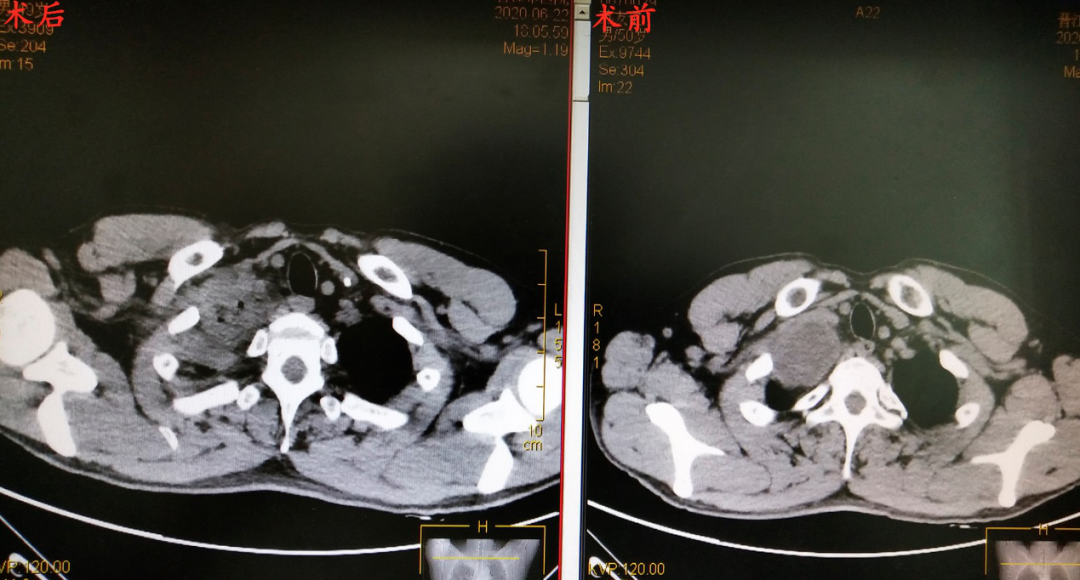

▲术前术后影像

手术当日,一场经过充分准备的“战斗”在手术室拉开序幕。在麻醉科的安全守护下,树兰医院朱理主任、晋医郑志民主任团队紧密配合,在两位主任强强联手下,在没有损伤到血管,没有劈开右侧锁骨、没有中转开胸的情况下,快速而巧妙地完成“战斗”。仅用时1个多小时,一场精彩的“探囊取物”顺利完成,出血仅几毫升,切口3-4cm的微创手术下,患者右上纵隔肿瘤被完整切除。术后病理诊断证实与术前判断一致,为神经鞘瘤。